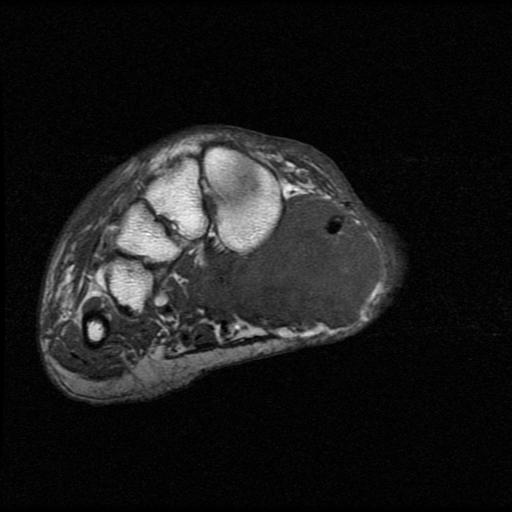

Calcaneum

Direct lateral approach